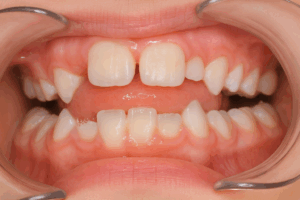

①上顎の前歯の本数が足りない(特に側切歯と呼ばれる2番目の歯)

上顎の側切歯の欠如は、およそ1から2%で生じるとされています。乳歯が抜けたのにも関わらず永久歯が生えてこない場合は、空隙が余ってしまい、真ん中が空いた状態が続きます。

↑ 前歯の本数が足りない場合、隙間は余ってしまいます